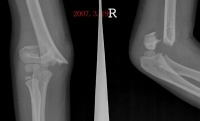

既往有外伤史,而伤后又未作任何处理,尤其是关节附近软组织损伤。如常发生于肱前肌

,则表现为肘关节区肿胀、压痛,肘关节被动主动活动受限。随后疼痛与肿胀消退,在肘关节前方可摸到一个包块,因包块出现而肘关节功能受到影响。另外也可见于三角肌、内收肌。

1.常有肘关节损伤史,多见于青少年。

2.早期以肘关节活动时疼痛为主,肘关节活动受限。

3.在肘关节周围可以摸到异常骨块,该骨块可逐渐增大,以后又可缓慢回缩至骨块成熟。

骨化好发与肱前肌,表现为肘关节区肿胀与疼痛,肘关节被动与主动活动均受限。疼痛与肿胀减退后在肘关节前方可以摸到一个界线清楚的硬的肿块。因肌肉无弹性,故肘关节伸屈受限;由于肿块的阻挡,屈曲也明显受限。

x线特征:受伤后不久可出现局限性肿快。伤后3-4周,在肿快内显示毛状致密象,其临近骨将显示骨膜反应。伤后6-8周,病变边缘部清楚地被致密骨质所包绕,而具有新生骨的外貌。软组织肿块的核心部有时显囊性变且逐渐扩大其内腔,到晚期而显出类似蛋壳状的囊肿。伤后5-6个月肿块收缩,因而肿块与邻近的骨皮质和骨膜反应之间显出x线透亮带。